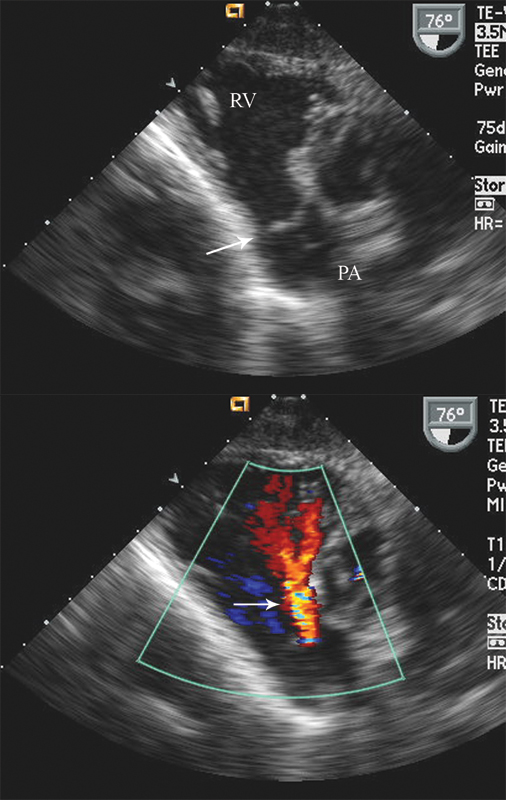

فحوصات تشخيصية لبعض امراض القلب والشرايين التاجية